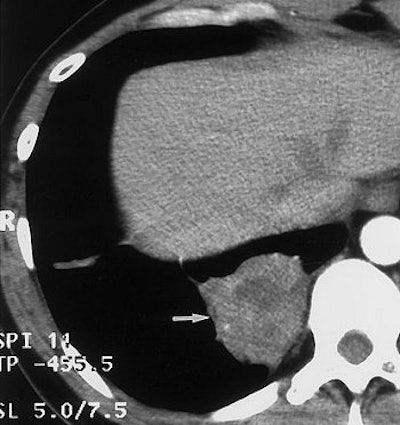

![]() |

| Image A. Contrast-enhanced nephrographic-phase CT scan shows dilated calices and thinning of the renal cortex (arrow). |

With conventional radiography, renal calcifications are a common manifestation of tuberculosis occurring in 25% to 44% of patients. CT is useful in determining the extent of renal and extra renal spread of the disease. Coalesced cortical granulomas and parenchymal scarring is apparent at CT, while fibrotic structures of the renal pelvis and ureters may be seen on contrast-enhanced CT, suggesting tuberculous infection.